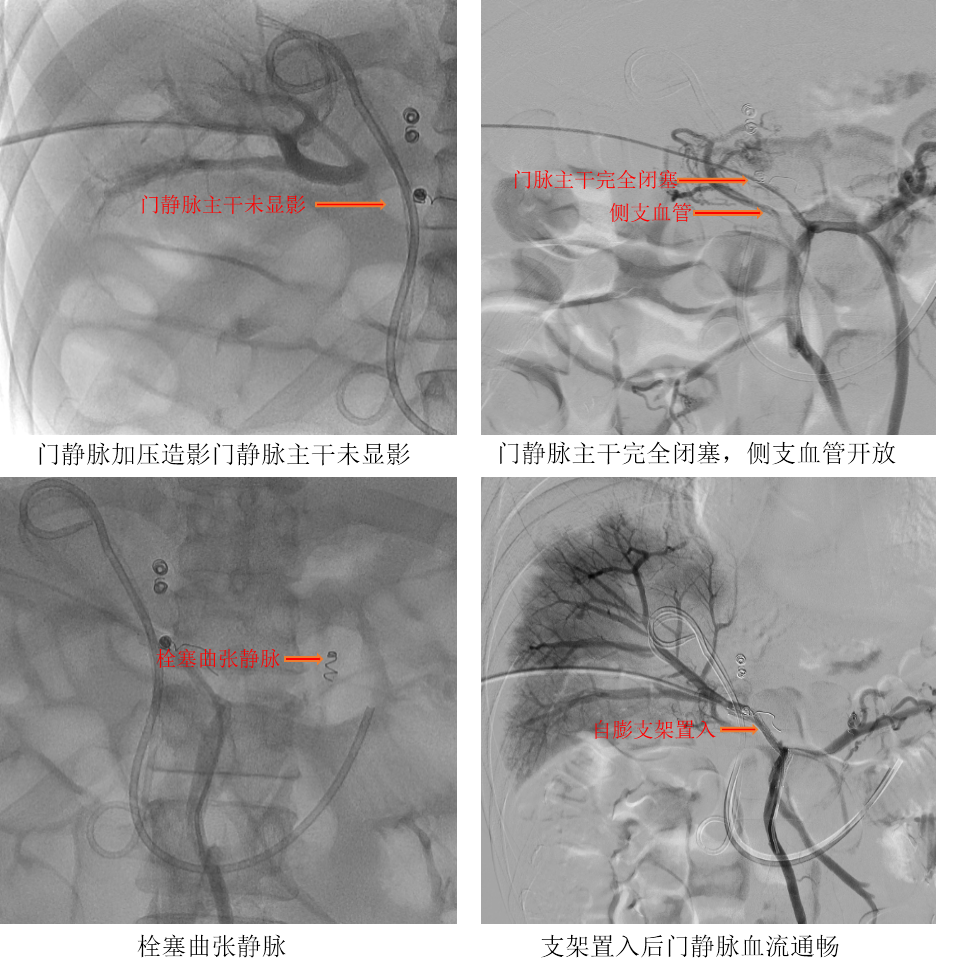

手术当日,张琳操作,团队医生黄鑫、廖勇、马军朋等密切配合,由于患者门静脉主干全程闭塞,术前CTA显示肝内门静脉显影不佳,仅见走形纤细的门静脉分支显影,左右主干均未显影,无法明确肝内门静脉是否闭塞,手术成功率较低,而且门静脉主干周围侧枝血管形成广泛,走形迂曲,主干开通难度大,风险极高。但随着手术的一步步推进,DSA造影显示肝内门静脉显影良好,肝内门静脉未闭塞,门静脉主干完全闭塞,在精细化介入操作下,团队反复尝试,最终通过门静脉主干狭窄段,完成这场“别人做不了的”手术。患者术后恢复顺利,门静脉通畅,压力下降,出血风险明显下降,肝功能改善,患者生活质量明显提升,为后续安全接受抗肿瘤治疗,打下了坚实的基础。